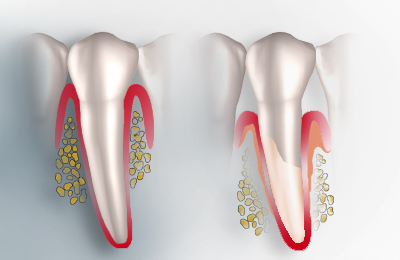

Hat sich der Zahnhalteapparat aufgrund einer Parodontitis abgebaut, kann dieser je nach Ausprägung des Abbaus wieder aufgebaut werden. Idealerweise sollte der neue, wieder aufgebaute Zahnhalteapparat sowohl in der Form als auch in der Funktion die gleichen Eigenschaften besitzen, wie der ursprüngliche.

Für die regenerative Behandlung ausgeprägter, parodontaler Defekte bieten sich unterschiedliche Methoden. Es gibt nur wenige Gewebe, die nach einem Defekt in der Lage sind, sich ohne Narbenbildung oder Funktionseinbußen zu regenerieren (wiederherzustellen). Wir bieten eine Regenerative Therapie mit Schmelzmatrixproteinen. Diese Proteine ermöglichen Ihrem Körper den natürlichen Zahnhalteapparat wieder herzustellen, indem sie die Prozesse, die während der Zahnentwicklung stattfinden, nachahmen. Die Wiederherstellung des Zahnhalteapparats (Wurzelzement, Faserbündel und Knochen) beginnt unmittelbar nach der Behandlung mit Schmelzmatrixproteinen und setzt sich über einen längeren Zeitraum fort.

Durch die Anwendung von regenerativen Methoden mit Schmelzmatrixproteinen soll vermieden werden, dass es zur Bildung von Narben- und Bindegewebe kommt.